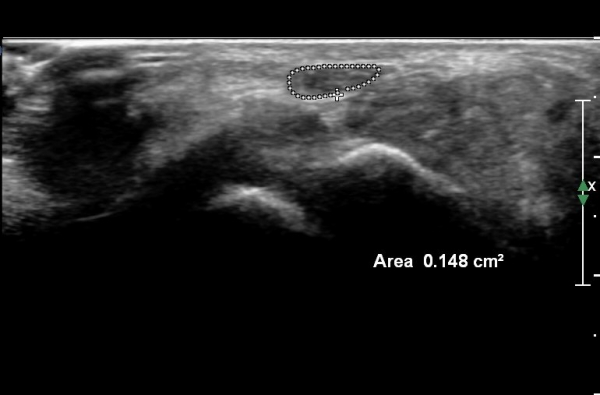

¼ö±Ù°ü ±ÙÀ§ºÎ(scaphoid, lunate level)¿¡¼ Á¤Á߽Űæ Ⱦ´Ü¸é°Ë»ç»ó Á¤Á߽ŰæÀÇ Àú¿¡ÄÚ ºÎÁ¾ÀÌ °üÂûµÊ.(»çÁø 2).